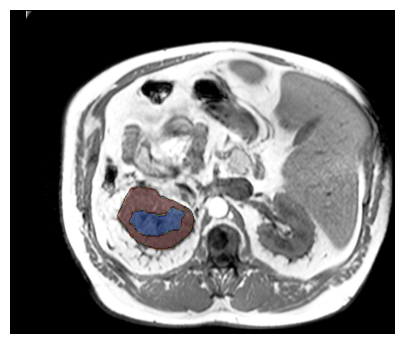

Purpose: To introduce a deep learning model capable of multi-organ segmentation in MRI scans, offering a solution to the current limitations in MRI analysis due to challenges in resolution, standardized intensity values, and variability in sequences. Materials and Methods: he model was trained on 1,200 manually annotated MRI scans from the UK Biobank, 221 in-house MRI scans and 1228 CT scans, leveraging cross-modality transfer learning from CT segmentation models. A human-in-the-loop annotation workflow was employed to efficiently create high-quality segmentations. The model's performance was evaluated on NAKO and the AMOS22 dataset containing 600 and 60 MRI examinations. Dice Similarity Coefficient (DSC) and Hausdorff Distance (HD) was used to assess segmentation accuracy. The model will be open sourced. Results: The model showcased high accuracy in segmenting well-defined organs, achieving Dice Similarity Coefficient (DSC) scores of 0.97 for the right and left lungs, and 0.95 for the heart. It also demonstrated robustness in organs like the liver (DSC: 0.96) and kidneys (DSC: 0.95 left, 0.95 right), which present more variability. However, segmentation of smaller and complex structures such as the portal and splenic veins (DSC: 0.54) and adrenal glands (DSC: 0.65 left, 0.61 right) revealed the need for further model optimization. Conclusion: The proposed model is a robust, tool for accurate segmentation of 40 anatomical structures in MRI and CT images. By leveraging cross-modality learning and interactive annotation, the model achieves strong performance and generalizability across diverse datasets, making it a valuable resource for researchers and clinicians. It is open source and can be downloaded from https://github.com/hhaentze/MRSegmentator.